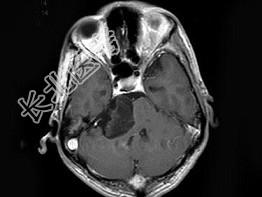

- 单项选择题男,38岁, 头痛半年余,MRI检查如图, 最可能的诊断是 ( )

A、听神经瘤

B、三叉神经瘤

C、表皮样囊肿

D、皮样囊肿

E、未见异常